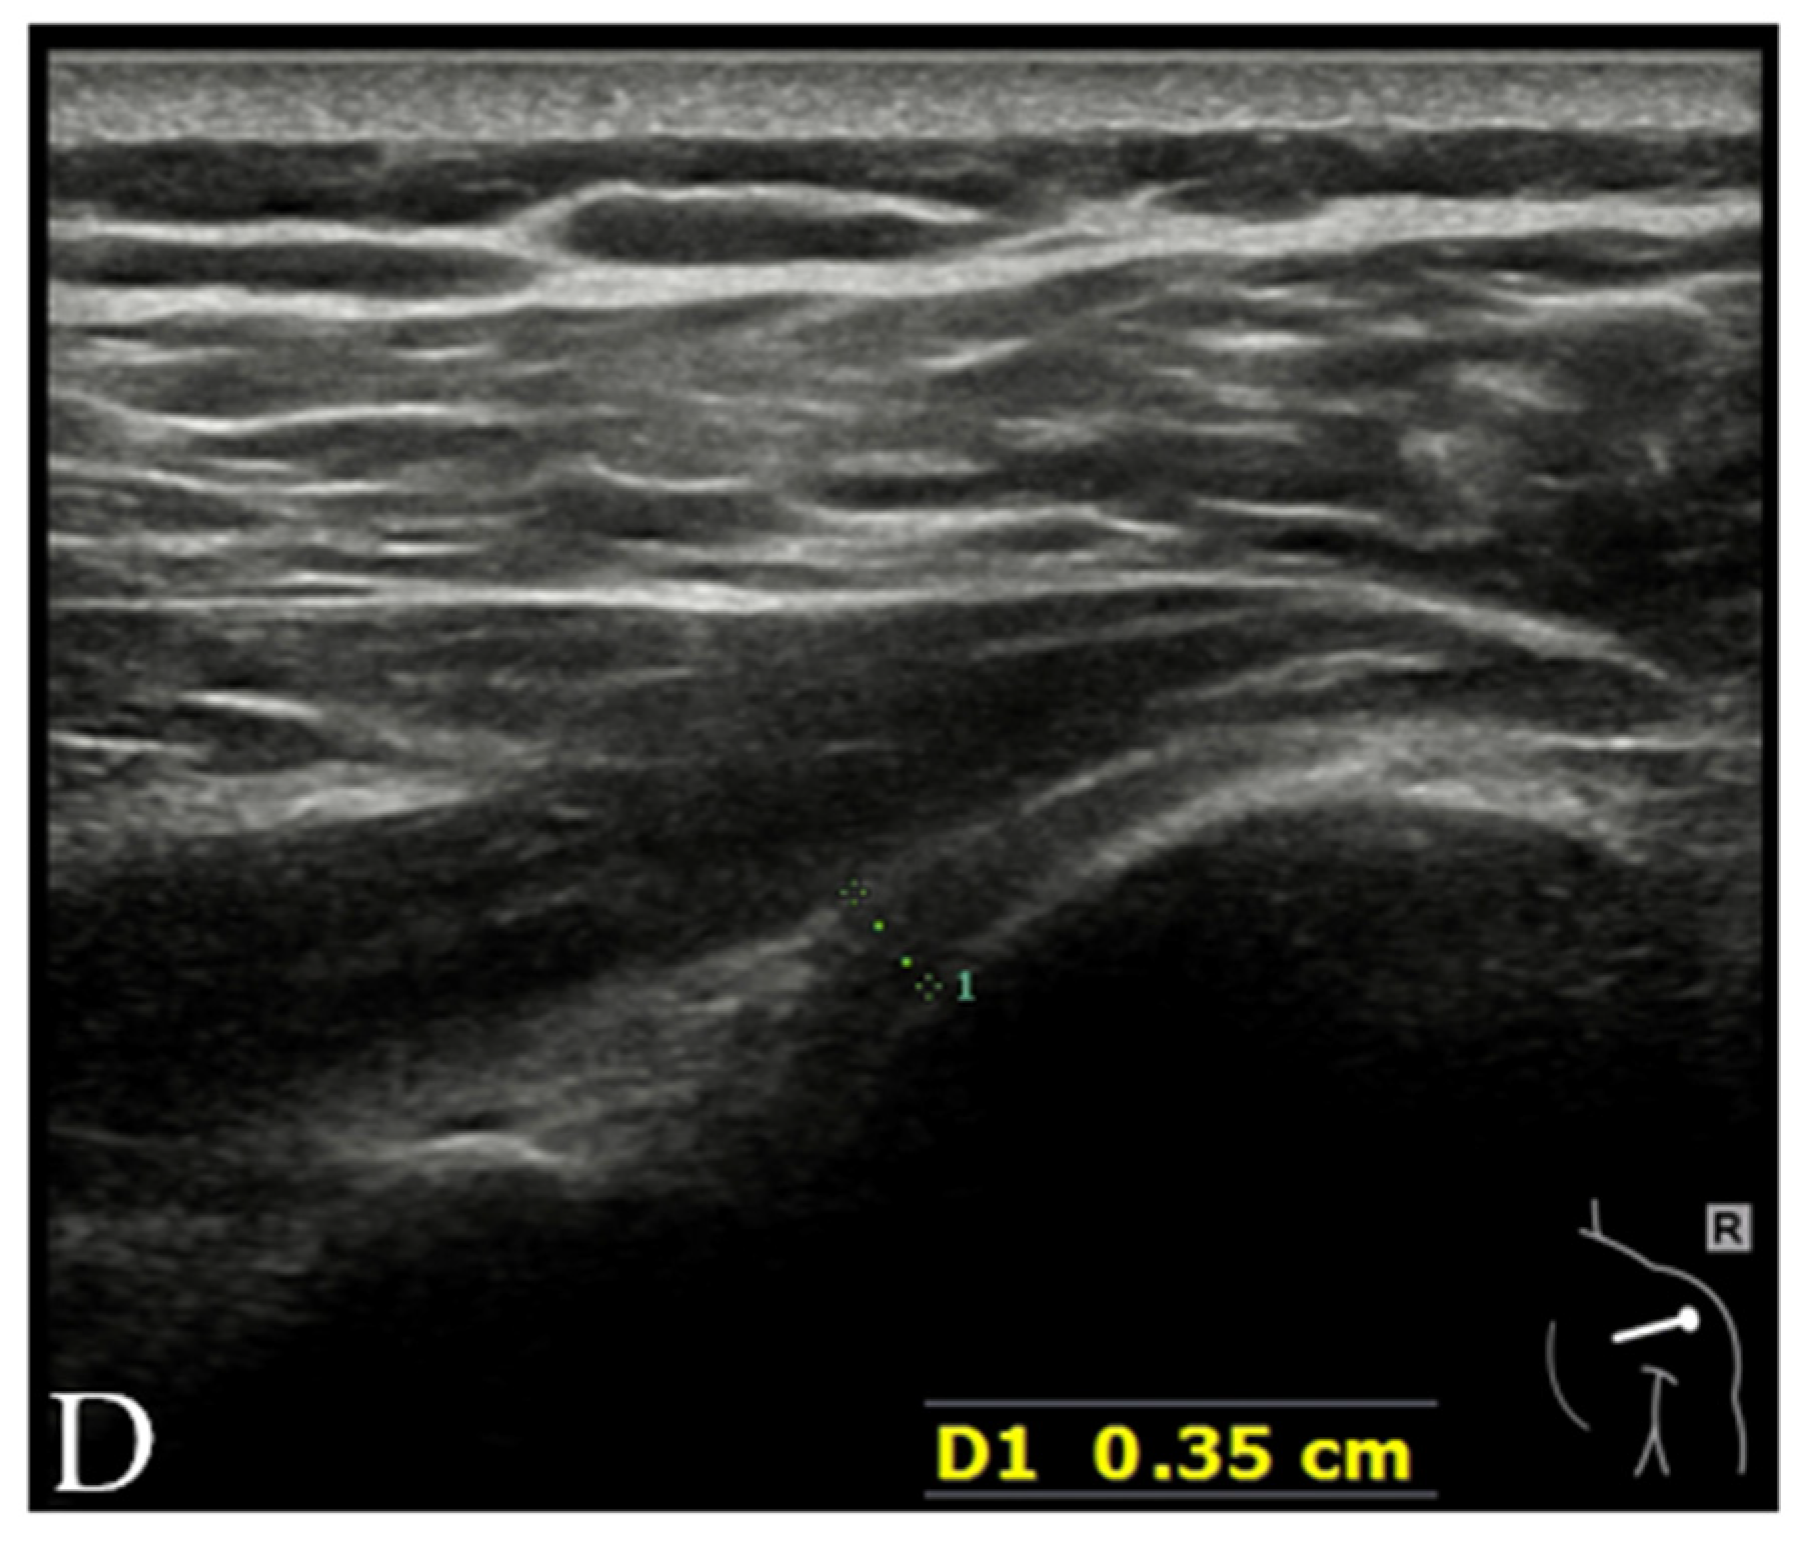

4.2. Adhesive Capsulitis (AC)